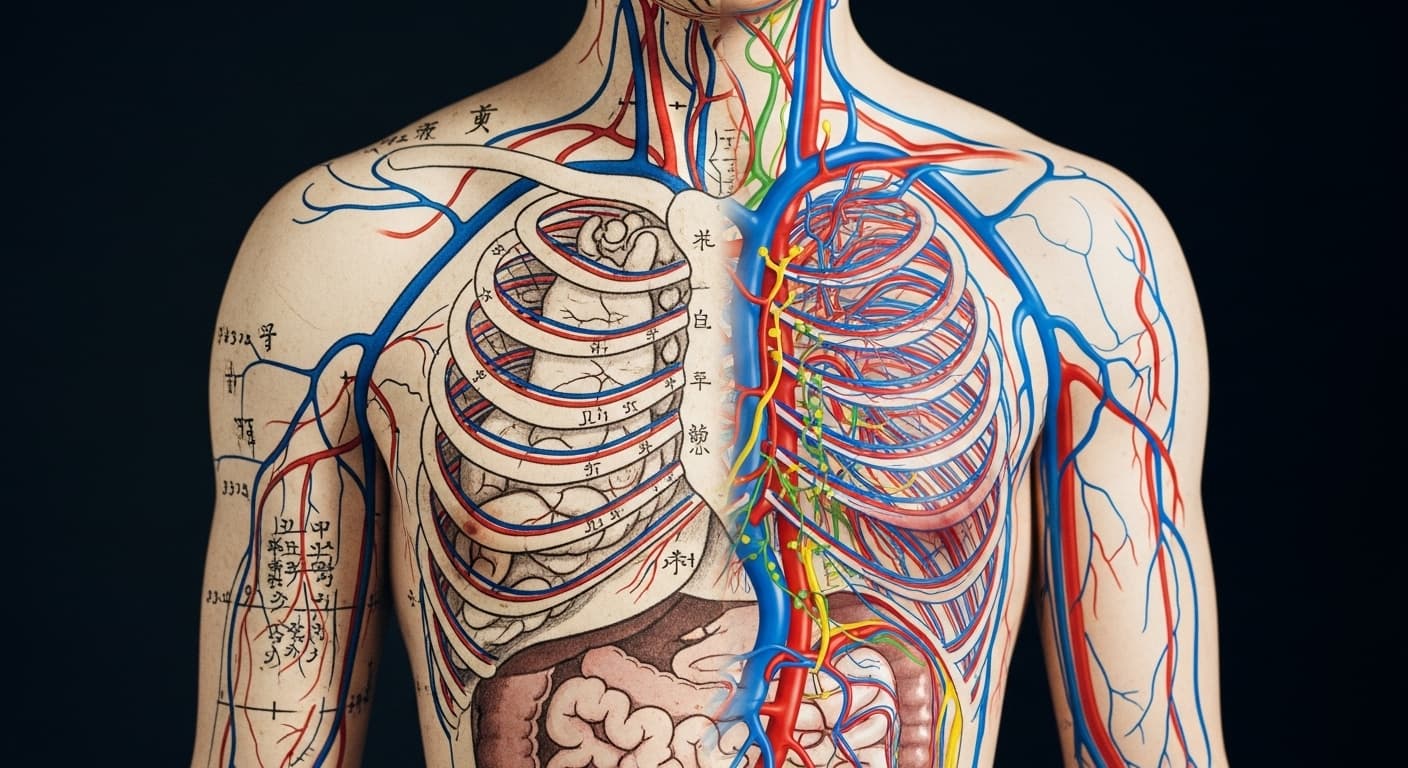

과학으로 풀어보는 가슴 림프 순환의 비밀

동의보감에서 말하는 '기체혈어'와 '담음'은 현대의학의 관점에서 보면 '림프액 정체로 인한 노폐물 축적 및 부종', 그리고 '미세 순환 장애'와 매우 유사한 개념으로 해석될 수 있습니다. 우리 몸은 이토록 정교하게 연결되어 있으니, 단순히 아픈 부위만 볼 것이 아니라 전반적인 순환과 균형을 돌보는 지혜가 필요한 거죠. 가슴 건강은 여성 건강의 중요한 지표이자, 몸 전체의 순환 건강을 알려주는 중요한 신호랍니다.

단순히 젖샘의 문제가 아니라, 오장육부의 균형이 깨지고 기혈 순환이 정체되면서 나타나는 전신적인 몸의 비명으로 본 거예요. 특히 ‘기체혈어(氣滯血瘀)’라고 해서, 기운의 흐름이 막히면 그 자리에 혈액까지 뭉치고 탁해지며, ‘담음(痰飮)’ 즉 불필요한 노폐물과 수분이 쌓이면서 붓고 통증을 유발한다고 설명했어요. 상상해보세요, 깨끗하게 흐르던 시냇물이 나뭇가지와 돌멩이로 막혀 고여버리면 물이 탁해지고 썩는 것처럼, 우리 몸속의 순환도 이와 같다는 거죠. 여성의 유방은 특히 감정의 변화와 월경 주기에 민감하게 반응하는 부위라, 스트레스나 화병 등으로 간의 기운이 울체되면 더 쉽게 붓고 아파질 수 있다고 보았답니다. 단순한 증상이 아니라, 내 몸의 섬세한 기운 흐름에 귀 기울여야 할 때라는 현명한 가르침인 거죠.